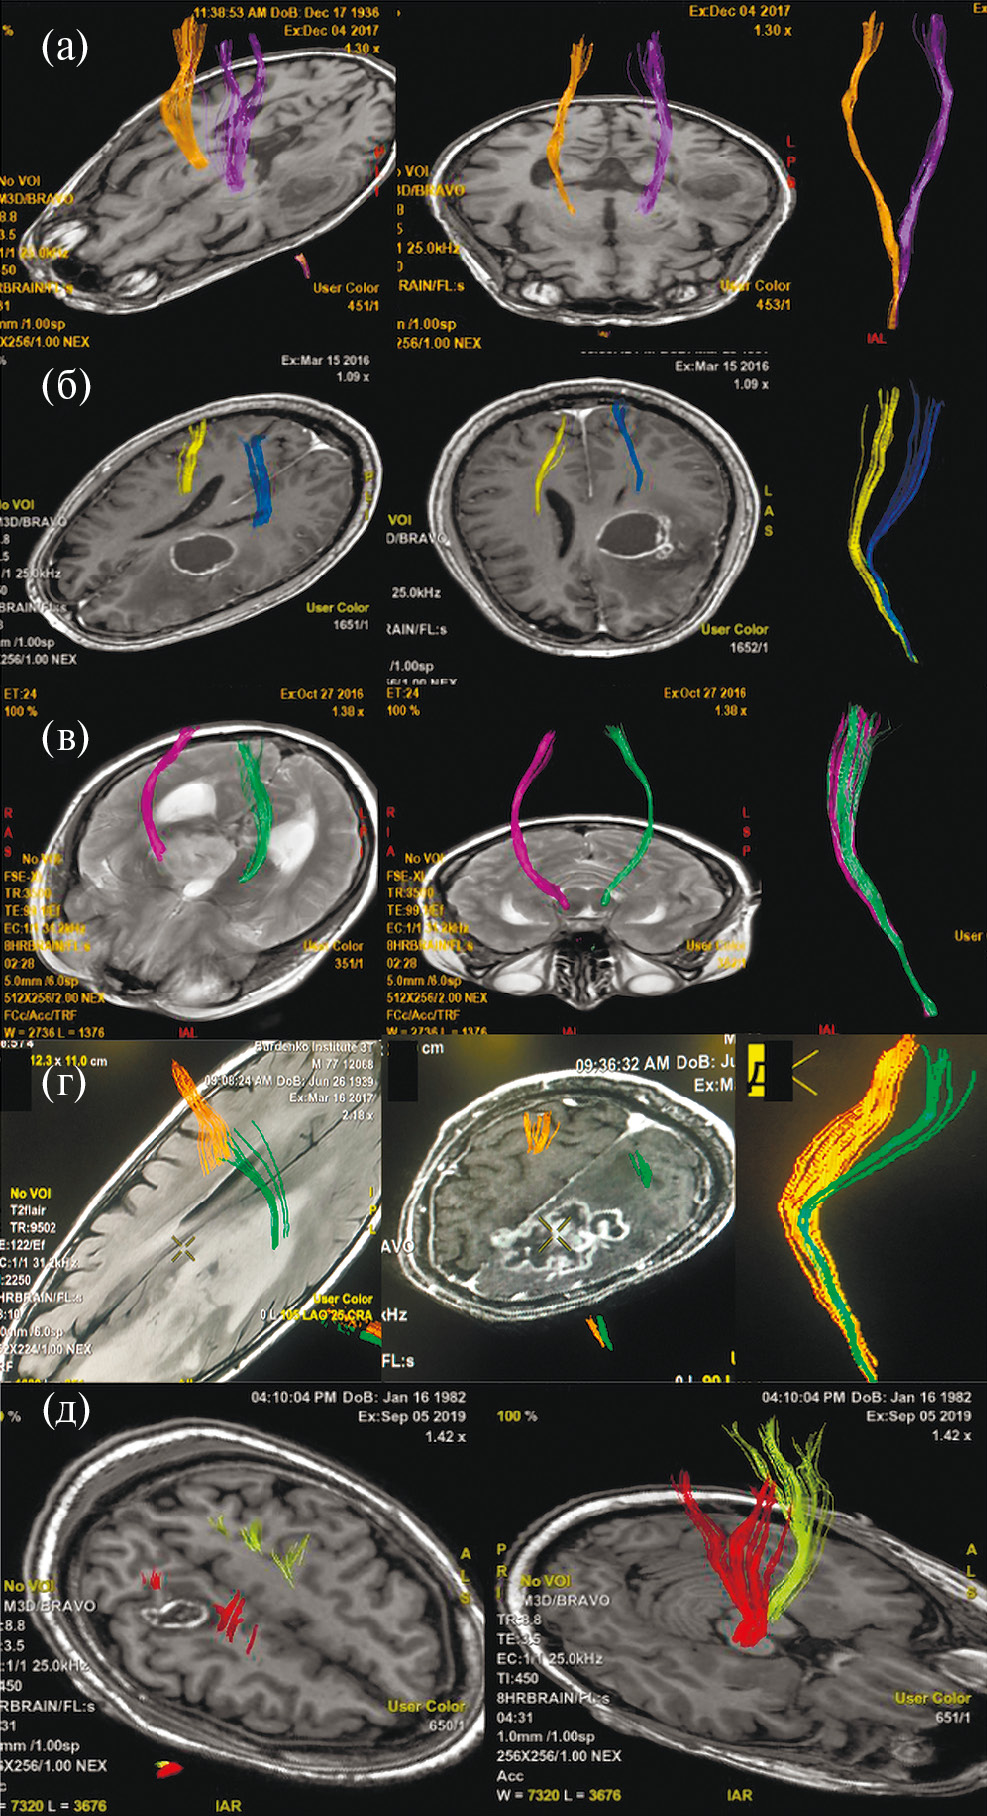

Учитывая локализацию процесса и клиническую картину заболевания, в качестве предоперационной подготовки пациенту были проведены фМРТ с визуализацией моторных зон и МР-трактография с построением КСТ (рис. 4).

Рис. 4. МРТ у пациента с внутримозговой опухолью правой теменной доли. (а, б) – данные фМРТ; (а) – оранжевым цветом обозначена корковая зона ноги, располагающаяся вовнутрь и на некотором отдалении от медиальной границы опухоли; (б) – представлена зона руки, прилегающая к переднему краю опухоли; (в, г) – данные МР-трактографии (CSD HARDI), использованный алгоритм построения позволил построить и разделить волокна КСТ, иннервирующие ногу (горчичный цвет), руку (фиолетовый), лицо (зеленый). Волокна КСТ прилегают к медиальному и переднему краям опухоли.

Fig. 4. fMRI (leg and arm areas) and MR-tractography (CSD HARDI, yellow – leg, purple – hand, green – facial muscles) before surgery.